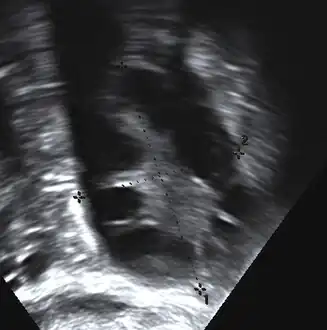

The syndrome acquired its most widely used name due to the common sign on ultrasound examination of multiple (poly) ovarian cysts. These "cysts" are in fact immature ovarian follicles. The follicles have developed from primordial follicles, but this development has stopped ("arrested") at an early stage, due to the disturbed ovarian function. The follicles may be oriented along the ovarian periphery, appearing as a 'string of pearls' on ultrasound examination.[86]

• Gynecologic ultrasonography, specifically looking for small ovarian follicles. These are believed to be the result of disturbed ovarian function with failed ovulation, reflected by the infrequent or absent menstruation that is typical of the condition. In a normal menstrual cycle, one egg is released from a dominant follicle – in essence, a cyst that bursts to release the egg. After ovulation, the follicle remnant is transformed into a progesterone-producing corpus luteum, which shrinks and disappears after approximately 12–14 days. In PCOS, there is a so-called "follicular arrest"; i.e., several follicles develop to a size of 5–7 mm, but not further. No single follicle reaches the preovulatory size (16 mm or more). According to the Rotterdam criteria, which are widely used for diagnosis of PCOS,[10] 12 or more small follicles should be seen in a suspect ovary on ultrasound examination.[21] More recent research suggests that there should be at least 25 follicles in an ovary to designate it as having polycystic ovarian morphology (PCOM) in women aged 18–35 years.[95] The follicles may be oriented in the periphery, giving the appearance of a 'string of pearls'.[96] If a high-resolution transvaginal ultrasonography machine is not available, an ovarian volume of at least 10 ml is regarded as an acceptable definition of having polycystic ovarian morphology. rather than follicle count.[95]

Most common names for this disease derive from a typical finding on medical images, called a polycystic ovary. A polycystic ovary has an abnormally large number of developing eggs visible near its surface, looking like many small cysts.[91]